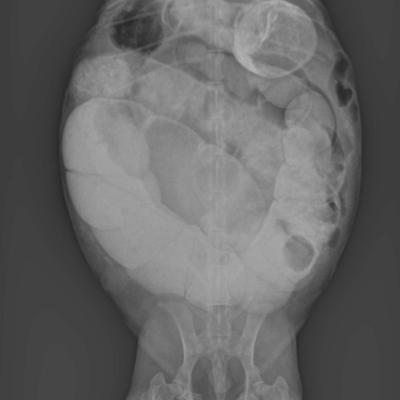

Oeufs de Tortue